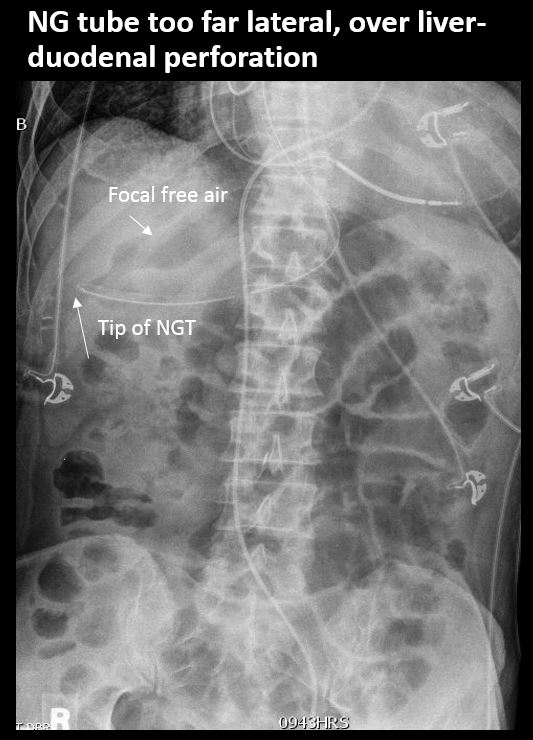

There is an NG/OG tube in place and properly positioned (the tip or sideport of the NG/OG tube is NOT above the GE junction and is NOT beyond the pyloris or otherwise malpositioned). |

No | NA |

There is scattered extraluminal air or an abnormal focal collection of air in the abdomen or pelvis. |

There is air in the retroperitoneum. |

Yes | NA |

There is retroperitoneal air outlining the right psoas muscle likely from duodenal perforation, from recent endoscopy. There are a few distended loops of small bowel in the mid and lower abdomen.

Notify the clinical team verbally and immediately about retroperitoneal air likely indicating duodenal perforation from recent endoscopy.